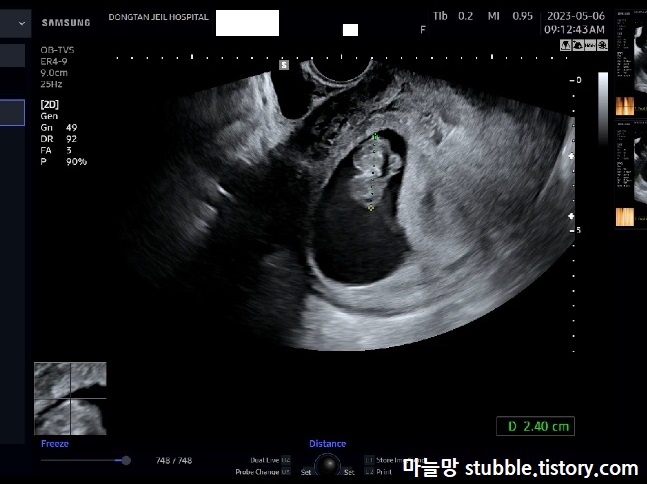

9주 2일 차 1분에 심장이 176회 정도 뛰고 있어요.

이렇게나 난황이 선명하게 보인적이 있었나 싶을 정도로 선명하게 보이는 난황과 거꾸로 물구나무서기 하고 있는 아기의 모습입니다. 마미톡으로 보면 팔이 흔들흔들 인사해 주는 것 같이 보이기도 했어요.

CRL(머리끝부터 꼬리뼈까지의 길이)을 재고 있는 우리 아기의 모습입니다.

2.40cm입니다.

무럭무럭 자라고 있었어요.